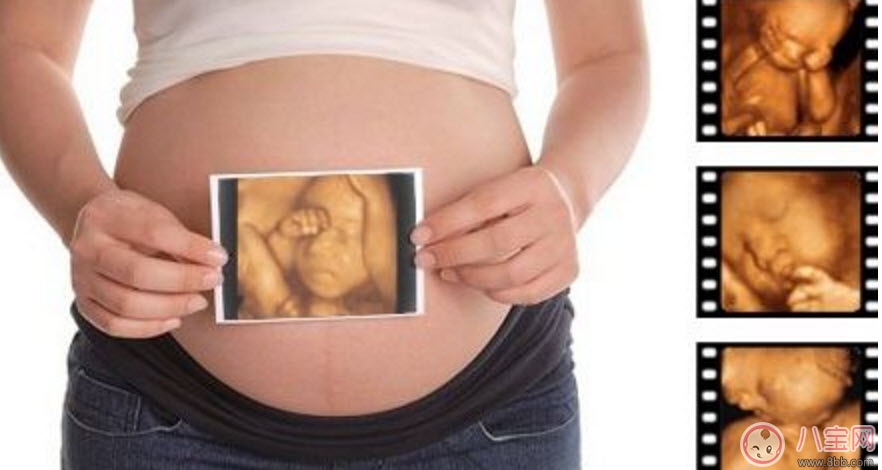

孕婦的羊水適量的話就可以做這項檢查。但是受胎兒體位、胎盤以及孕期不同等方面的因素影響,專家建議最佳做四維彩超的時間應該是12-30周,這個時期就可以完全獲取到胎兒的面部以及身體等結(jié)構(gòu)的圖像。懷孕十個月的時候里最少要做3次的四維彩超,時常觀察胎兒成長。

1、一般整個孕期做三次四維彩超,懷孕的22~26周做四維彩超最佳,但是具體時間也是因人而異的。

2、孕婦在22-26周的階段,做四維彩超不需要憋尿,也不需要空腹。孕婦指需要在規(guī)定的時間內(nèi)到醫(yī)院進行檢查即可。

3、在四維彩超檢查前,孕婦最好將自己的上衣和褲子分開穿。而在四維彩超的檢查中,醫(yī)生主要是通過檢查的儀器,對胎兒當前的面部發(fā)育,還有心臟,大腦,脊椎等有沒有存在發(fā)育缺陷的情況進行一個檢查。

4、做四維彩超時,孕媽媽一定要保持良好的心態(tài),整個做檢查過程大概會持續(xù)20分鐘左右。